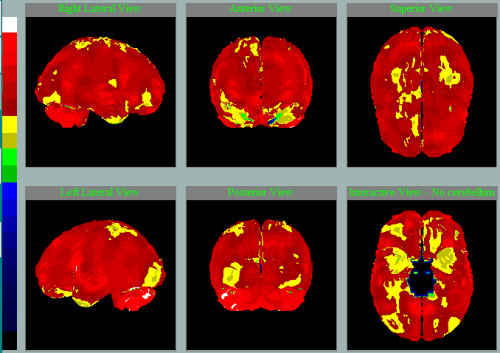

Různé nemoci na SPECT mozku s charakteristickými vzorci hypoperfúze

Frontotemporální lobární degenerace

Pedevším temporální hypoperfúze vlevo.

Především frontální hypoperfúze oboustranně.

Především frontotemporální hypoperfúze vlevo.

Nemoc s Lewyho tělísky